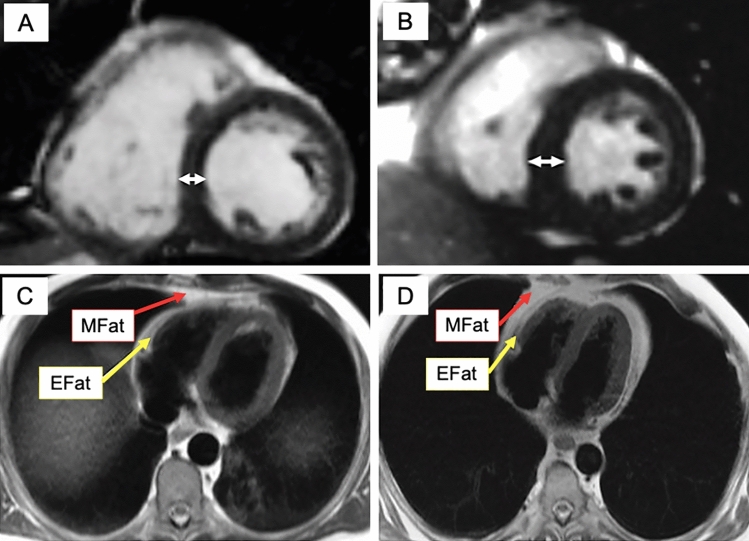

Methods: LV characteristics, epicardial (EAT), and mediastinal adipose tissue (MAT) were measured from 29 normoglycemic, normotensive males with CO but without general obesity (waist circumference >100 cm, body mass index (BMI) <30 kg/m2) and 18 non-obese male controls.

Results: LV maximal wall thickness (LVMWT) and IAT but not LV mass or volumes were increased in CO subjects compared to controls (LVMWT, 12.3±1.2 vs. 10.7±1.5 mm, p < 0.001; EAT, 5.5±3.0 vs. 2.2±2.0 cm2, p = 0.001; MAT, 31.0±12.8 vs. 15.4±10.7 cm2, p < 0.001). The LVMWT was ≥12 mm in 69% of subjects with CO and 22% of controls (p = 0.002). In CO suspects, EAT correlated inversely with LV end-diastolic volume index (r = - 0.403, p = 0.037) and LV stroke volume (SV) (r = - 0.425, p = 0.027). MAT correlated inversely with SV (r = - 0.427, p=0.026) and positively with LVMWT (r = 0.399, p = 0.035). Among CO subjects, the waist-to-hip ratio (WHR) was an independent predictor of LVMWT (B = 22.4, β = 0.617, p < 0.001). The optimal cut-off with Youden's index for LV hypertrophy was identified at WHR 0.98 (sensitivity 85%, specificity 89%).

Conclusions: CO independent of BMI is associated with LV hypertrophy and intrathoracic adipose tissue contributing to cardiovascular burden.